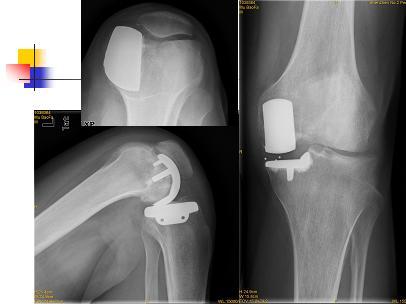

膝关节单髁置换

男性,25岁,行走疼痛2年。

术中见单髁破坏严重,病理为:剥脱性骨软骨炎